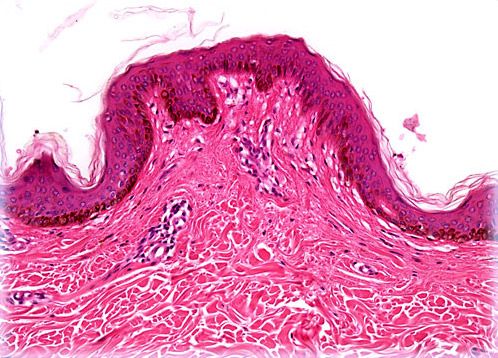

Heavily Pigmented Skin